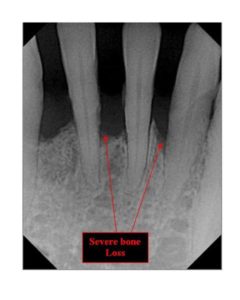

A destructive infection of the gum and underlying bone. It is gingivitis that has gotten out of control and has started to destroy the connection between the gum and the tooth. It is characterized by red, swollen and bleeding gums and will result in tooth loss if it is not treated. The infection causes the bone and ligament which hold the tooth in place to be destroyed. It is also known as periodontal disease and Pyorrhea. How aggressively the infection destroys the bone and gum which support the teeth is influenced by whether or not the patient smokes, if they are diabetic, if they are genetically predisposed, if they are on certain medications and if they clench and grind their teeth. Gum infection has also been linked to cardiovascular disease, stroke, low birth weight and preterm newborns, difficulty in controlling diabetes and recent evidence suggests it may affect Alzheimer’s and upper respiratory tract infections.